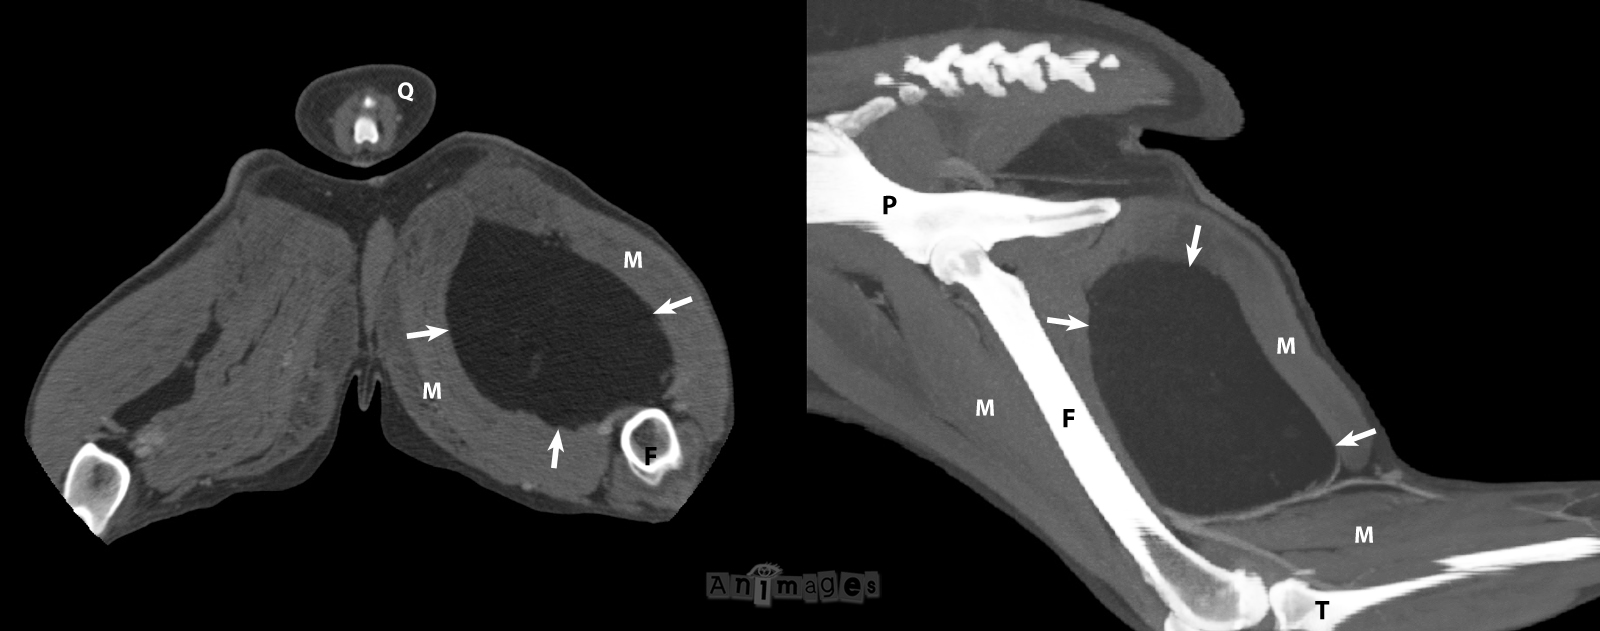

Les lipomes représentent souvent une trouvaille fortuite chez le chien (surtout gériatrique). Dans certains cas, ils peuvent se développer dans un membre et provoquer une boiterie. Ces lipomes peuvent être bien encapsulés ou plutôt infiltrants, et de localisation intermusculaire ou intramusculaire. L’échographie représente un test utile lorsque le lipome est petit, permettant de confirmer son échotexture, d’en recueillir un échantillon cellulaire (cytoponction ou biopsie) pour exclure un processus malin (ex. lorsque son opacité adipeuse est moins évidente à la radio ou lors de suspicion de liposarcome). La tomodensitométrie (CT, scanner) représente toutefois un test globalement plus utile car permet d’en définir plus précisément la localisation et l’étendue, surtout lorsque ce lipome est volumineux, et les caractéristiques tissulaires. Les lipomes ont au CT un niveau d’atténuation – ou densité – qui se différencie facilement des sarcome et autres tumeurs des tissus mous. La capsule du lipome peut être visualisée dans bien des cas, sauf évidemment pour les lipomes « infiltrants ». Le CT aide aussi à mieux planifier la chirurgie et déterminer si celle-ci est réalisable. Ces images CT (ci-bas) d’un autre chien montrent un lipome hypoatténuant (flèches) au contours lisses et bien définis, repoussant les muscles (M) de la cuisse. L’image de gauche représente un plan transverse aors que celle de gauche est une image reformatée en plan sagittal de la cuisse. Q= queue, F=fémur, P=pelvis, T=tibia.